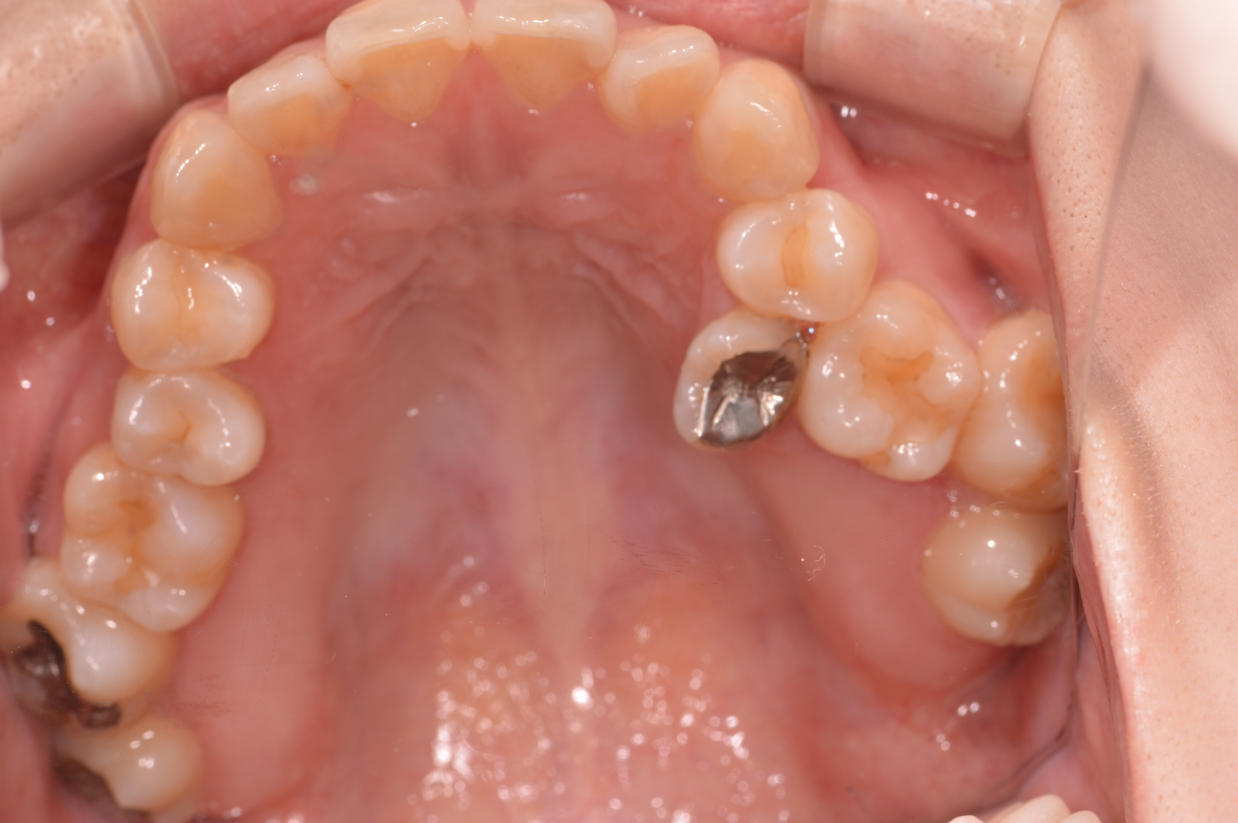

症例2

| 来院時の主訴 | 「右上の、内側に生えている歯が邪魔。」 |

| 矯正法 | 上の歯2本、下の歯2本、親知らず3本を抜歯しての矯正 |

| 通院期間 | 3年6ヶ月 |

| ここがこだわりのポイント!☝ | こちらの患者様は上の歯が1本内側に生えていましたが、奥歯の噛み合わせの方が問題でした。ハサミ状咬合といい、奥歯が極端に外側に向いており、下の歯と噛み合っていない状態でした。ハサミ状咬合は長期的にみると、前歯に大きな負担がかかったり、磨きにくい事による虫歯や歯周病になりやすいなどのリスクがあります。治療期間はかかりましたが、見た目の良さだけでなく、機能的にも改善しました。 |